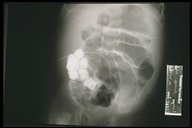

A catheter is introduce through the fistula for fistulogram

Plain X-ray showed that the catheter is located in the suprapubic region which is most likely in the bladder

Contrast study fills the bladder proving the fistula to be a patent urachus